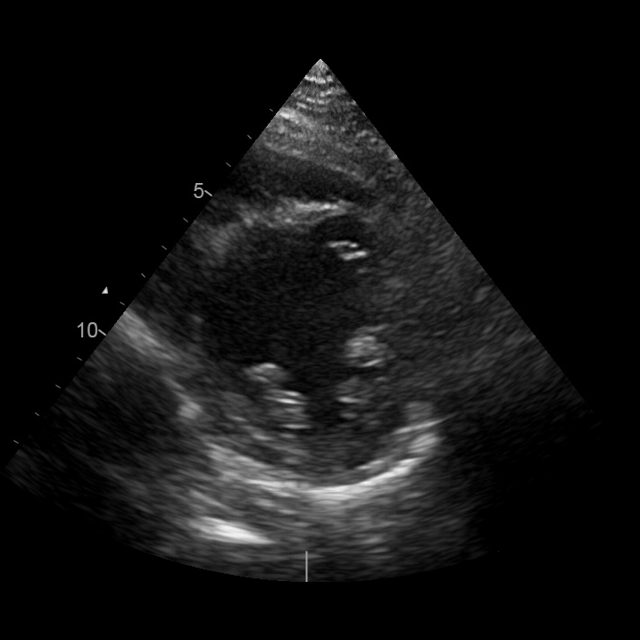

We structure each study to mirror clinical reading: a pretrained classifier assigns standardized views, followed by quantitative measurement extraction. Views are categorized using the American Society of Echocardiography (ASE)–defined classes (mitchell2019guidelines). To extract quantitative parameters, we crop the clinically annotated measurement overlays from the image and transcribe them into structured JSON using Qwen2.5-VL-72B (qwen2.5-VL; Qwen2VL). The resulting fields include chamber dimensions, transvalvular gradients, and Doppler ratios.(Fig. 2a). Extraction fidelity was verified by manual review.

EchoGround-MIMIC

The resulting dataset, EchoGround-MIMIC, comprises 19,065 image–text pairs from 1,572 patients. Each image is annotated with abnormality labels spanning 9 ASE-defined disease categories (Fig. 3, left) graded from normal to severe (see appendix A.5.1, Fig. 8), as well as one of 22 ASE-standard views (Fig. 3, right). In addition, the dataset includes structured measurements and measurement-grounded captions. This unified resource anchors echocardiography interpretation in standardized views, quantitative measurements, and clinical guidelines, supporting the development and evaluation of multimodal models.